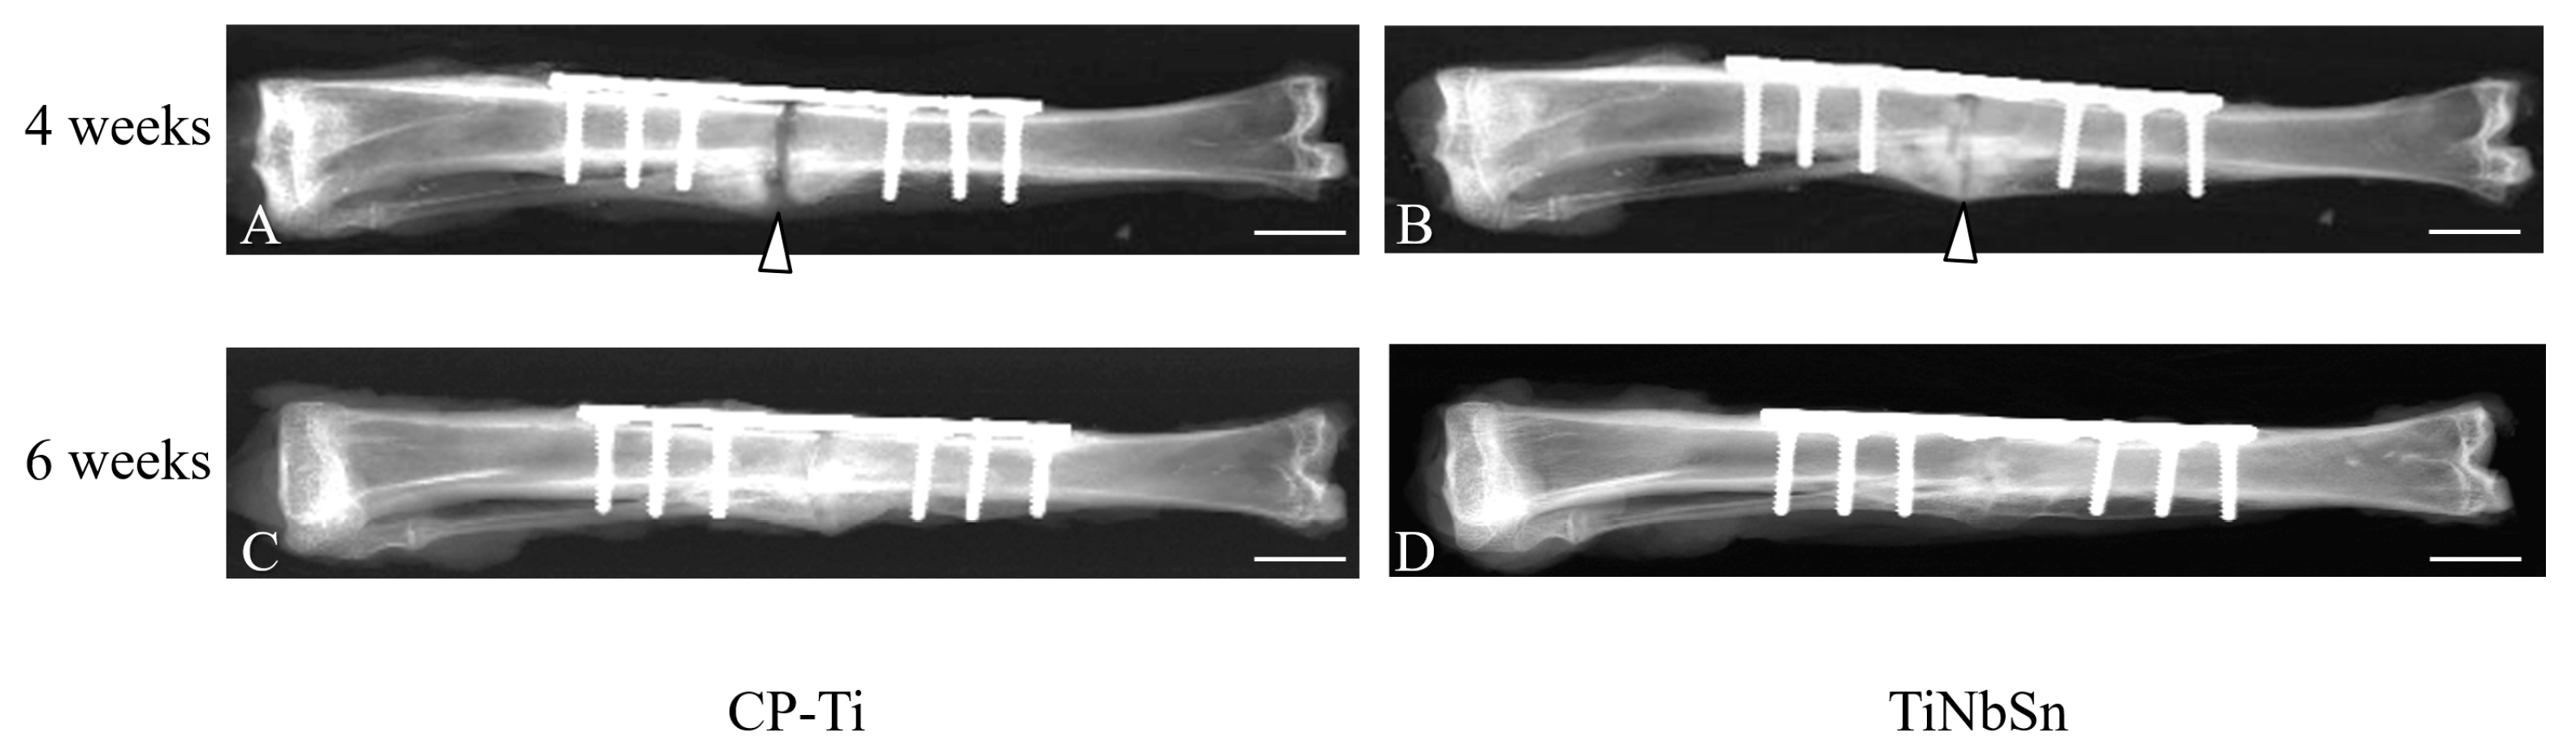

- Fujisawa, H.; Mori, Y.; Kogure, A.; Tanaka, H.; Kamimura, M.; Masahashi, N.; Hanada, S.; Itoi, E. Effects of intramedullary nails composed of a new beta-type Ti-Nb-Sn alloy with low Young’s modulus on fracture healing in mouse tibiae. J. Biomed. Mater. Res. B 2018, 106, 2841–2848. [Google Scholar] [CrossRef] [PubMed]

- Kogure, A.; Mori, Y.; Tanaka, H.; Kamimura, M.; Masahashi, N.; Hanada, S.; Itoi, E. Effects of elastic intramedullary nails composed of low Young’s modulus Ti-Nb-Sn alloy on healing of tibial osteotomies in rabbits. J. Biomed. Mater. Res. B Appl. Biomater. 2019, 107, 700–707. [Google Scholar] [CrossRef] [PubMed]

- Mori, Y.; Fujisawa, H.; Kamimura, M.; Kogure, A.; Tanaka, H.; Mori, N.; Masahashi, N.; Aizawa, T. Acceleration of Fracture Healing in Mouse Tibiae Using Intramedullary Nails Composed of β-Type TiNbSn Alloy with Low Young’s Modulus. Tohoku J. Exp. Med. 2021, 255, 135–142. [Google Scholar] [CrossRef] [PubMed]

- Koguchi, M.; Mori, Y.; Kamimura, M.; Ito, K.; Tanaka, H.; Kurishima, H.; Koyama, T.; Mori, N.; Masahashi, N.; Aizawa, T. Low Young’s Modulus TiNbSn Alloy Locking Plates Accelerate Osteosynthesis in Rabbit Tibiae. Tohoku J. Exp. Med. 2023, 261, 199–209. [Google Scholar] [CrossRef] [PubMed]